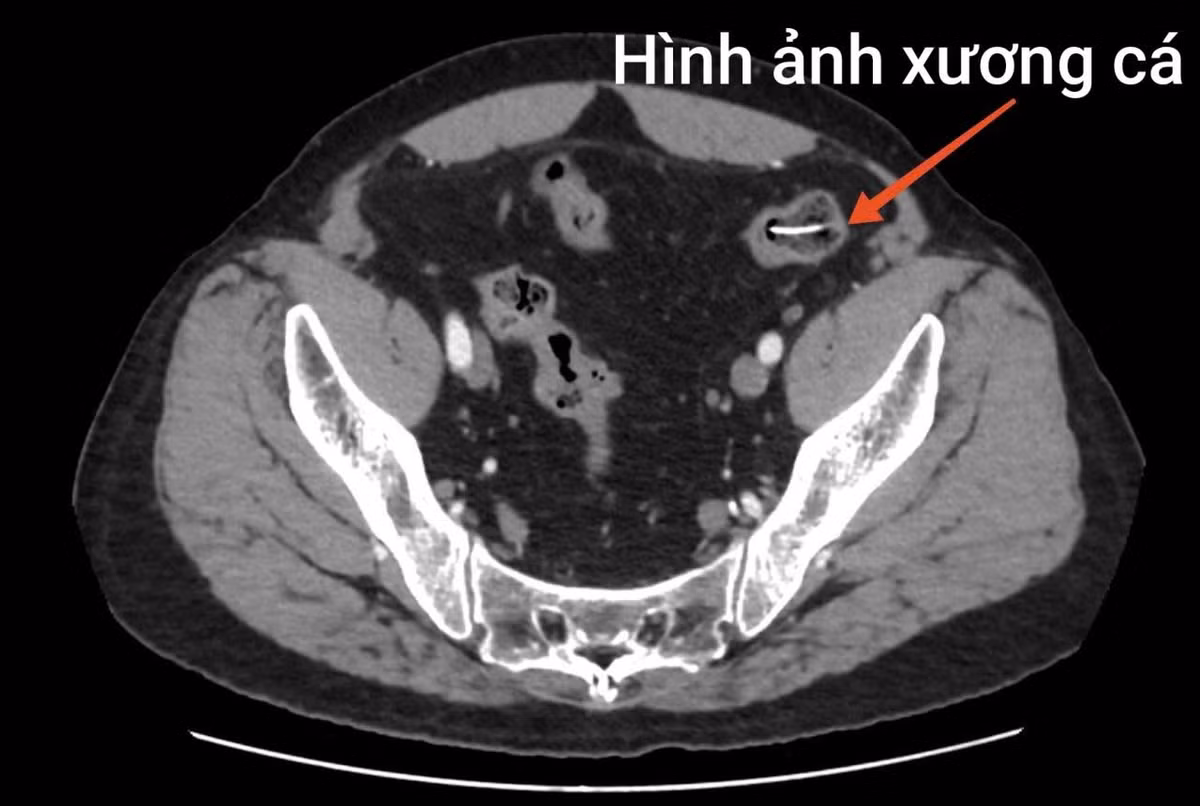

Trong quá trình mổ, ê-kíp phẫu thuật phát hiện ổ bụng bẩn nặng, nhiều giả mạc, dịch ổ bụng đục, tập trung ở hạ vị – hố chậu phải. Tại vị trí ruột non cách góc hồi manh tràng khoảng 1 mét, có dị vật hình xương cá dài khoảng 4cm chọc thủng ruột non tạo thành 01 lỗ thủng đường kính khoảng 0,5cm.

Xương cá dài 4 cm đâm thủng ruột non người đàn ông/ Ảnh BV Bệnh Nhiệt đới Trung ương